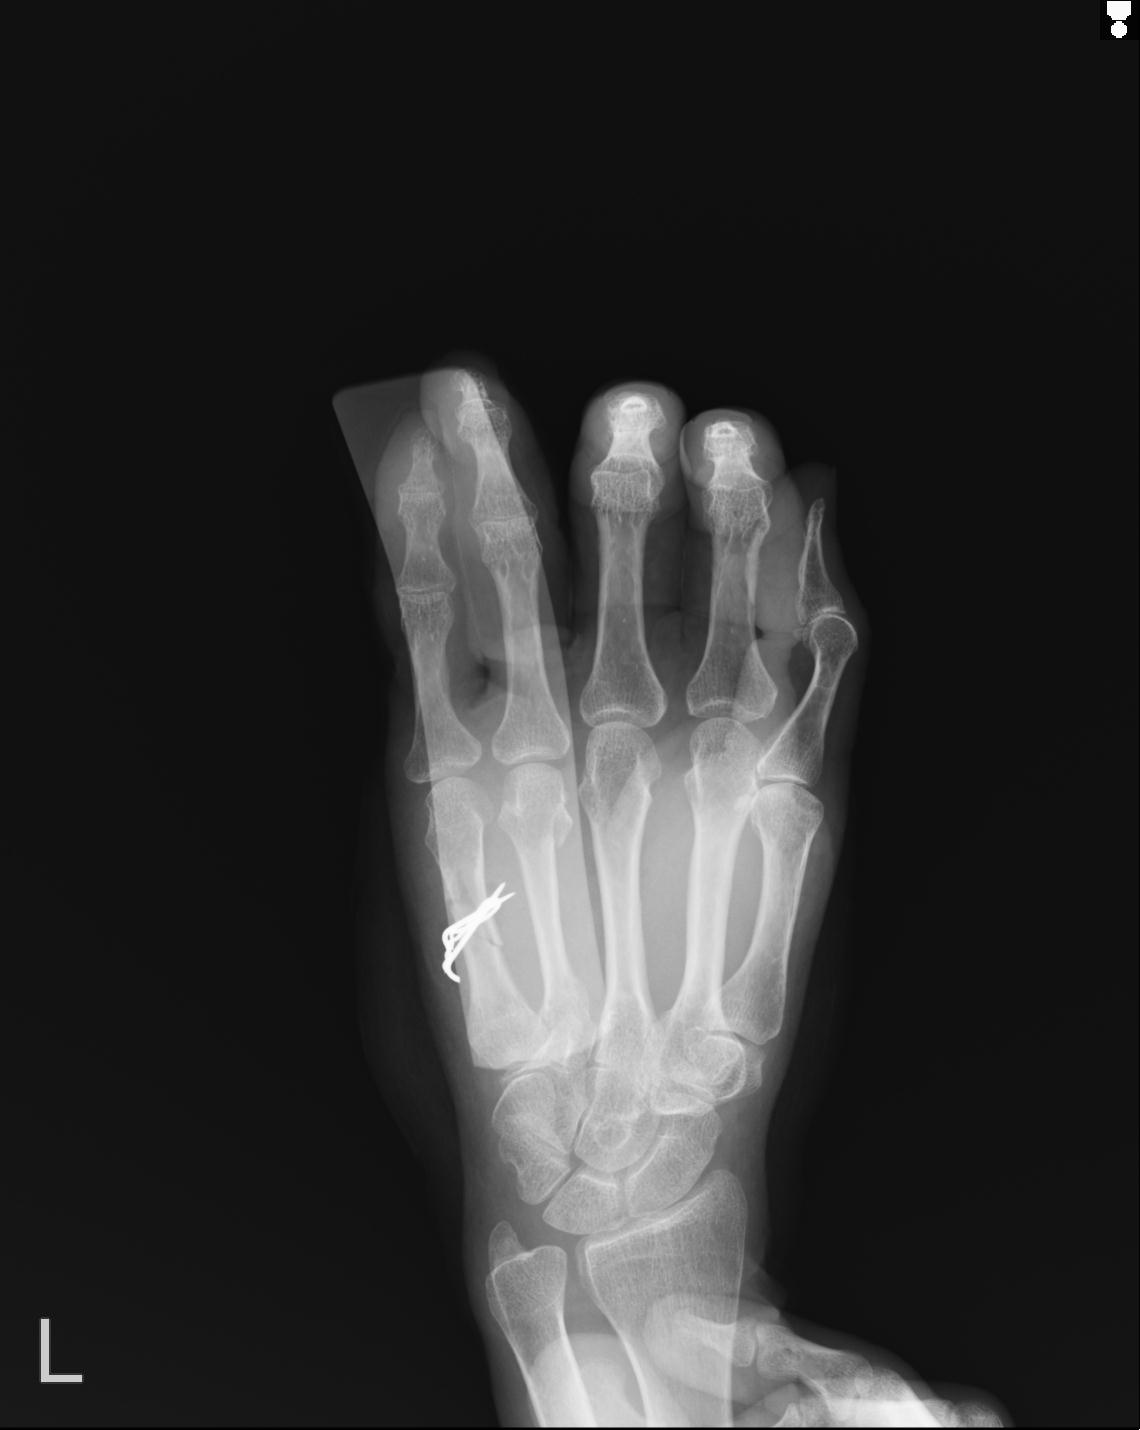

56476 8/28 4R 1/21 2R 左足関節 デジカメ写真 72歳女性 右足関節AS